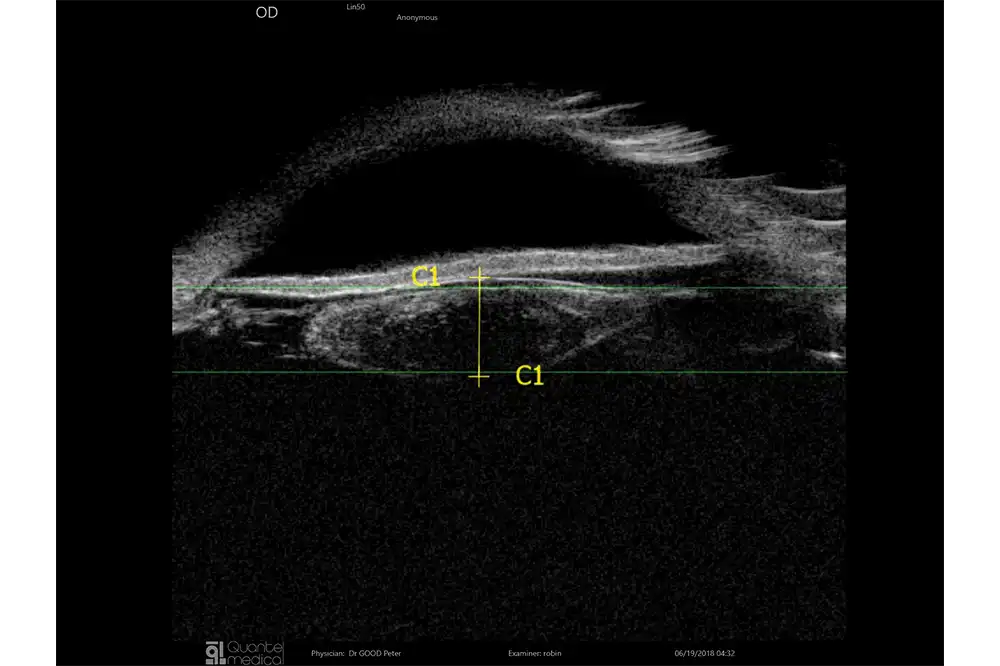

De sondes B15, B20-5A en UBM zijn uitgerust met een IMUv®-bewegingssensor die essentiële real-time informatie biedt, zoals:

- De positie van de sonde op het oog

- De visualisatie van het waargenomen gebied

Dit helpt de operator om onderzoeksgebieden eenvoudiger en sneller te identificeren. Deze technologie is gepatenteerd en exclusief voor Quantel Medical.